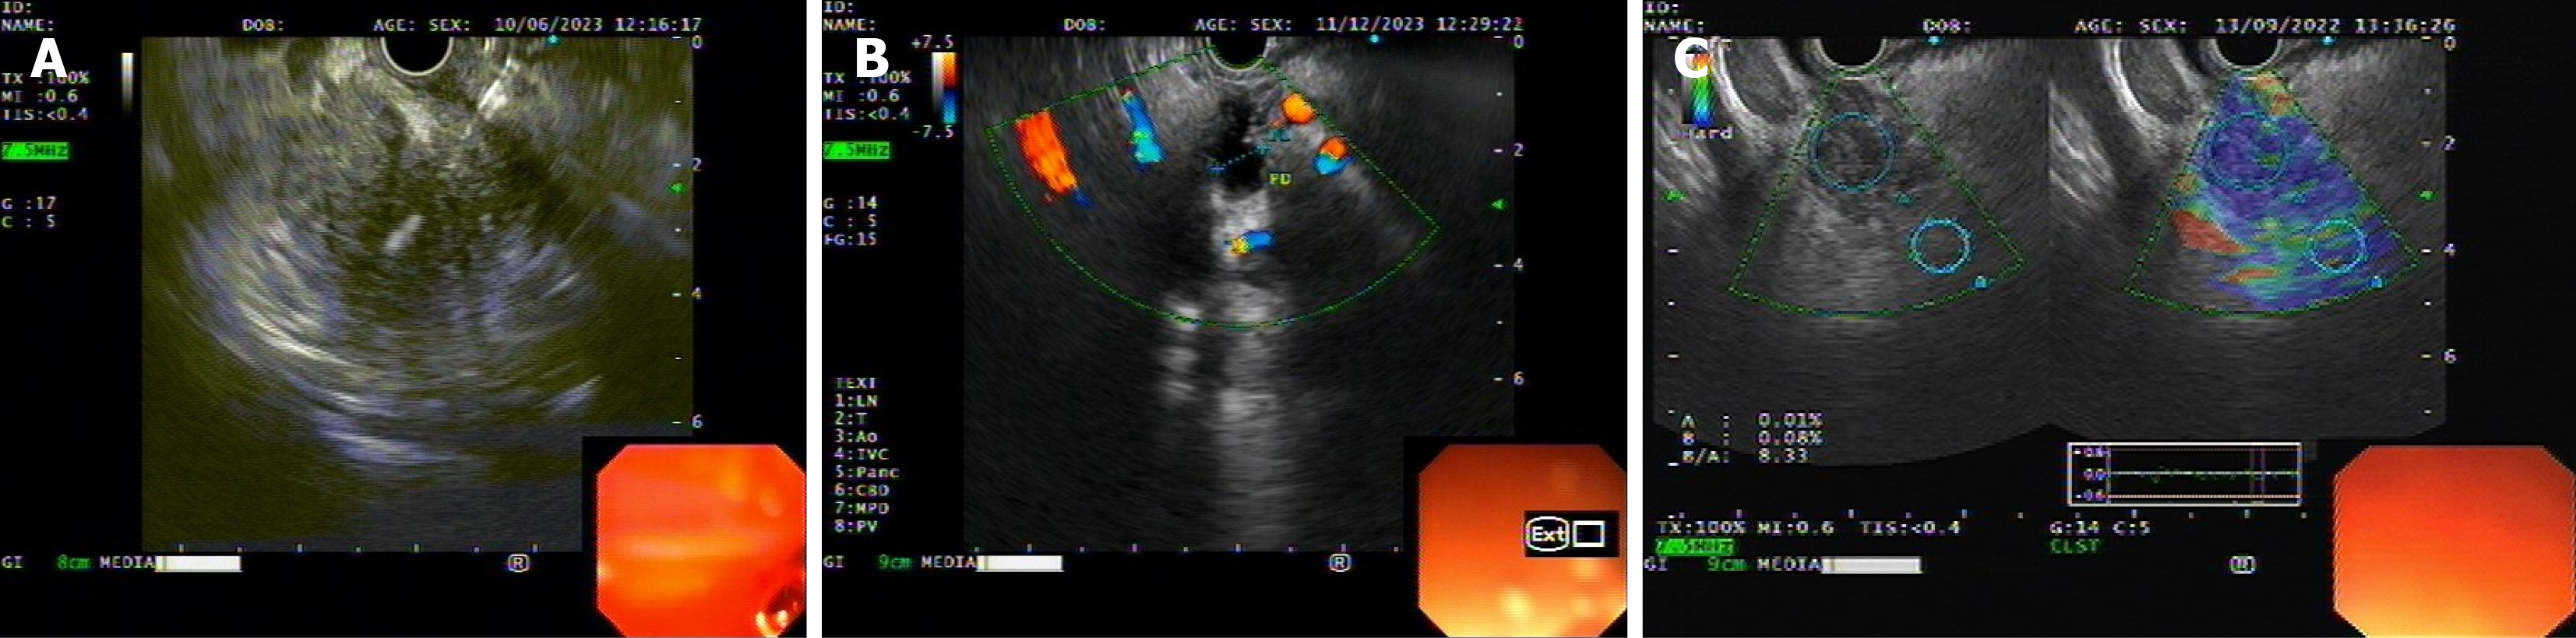

Figure 1 Representative endoscopic ultrasound imaging findings of pancreatic head lesions.

A: Endoscopic ultrasound (EUS)-fine needle biopsy from a hypoechoic mass in pancreatic head; B: Dilated and interrupted pancreatic duct in a case of pancreatic cancer (EUS image); C: Strain ratio in EUS-elastography of a pancreatic head lesion.